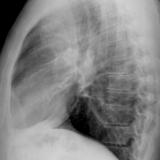

Case 1b

Date: 10/01/2006

Views: 3093